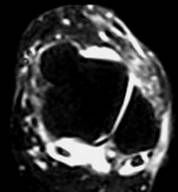

| Рис 3. Саггитальная плоскость сканирования. Т2 и Т1 ВИ. Стрелками указаны повышенное скопление жидкости в переднем и заднем заворотах, в полости суставов – большеберцово-таранном и таранно-пяточном. Повреждение каких-либо связок можно лишь предположить. |